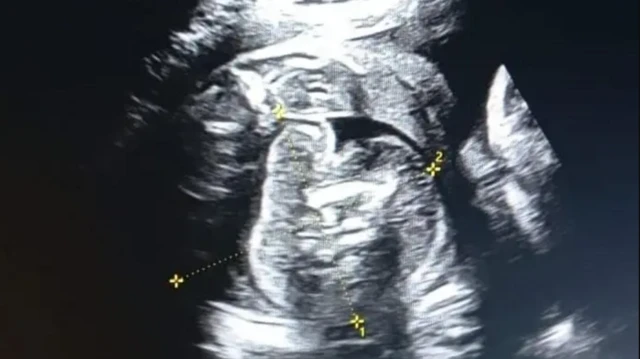

ਤਸਵੀਰ ਸਰੋਤ, quasim sheikh

ਬੁਲਢਾਣਾ ਦੀ 32 ਸਾਲਾ ਔਰਤ ਜੋ 8 ਮਹੀਨਿਆਂ ਦੀ ਗਰਭਵਤੀ ਹੈ, ਉਹ ਸਰਕਾਰੀ ਹਸਪਤਾਲ ਸੋਨੋਗ੍ਰਾਫੀ ਕਰਵਾਉਣ ਪਹੁੰਚੀ ਸੀ।

ਜਾਂਚ ਤੋਂ ਪਤਾ ਲੱਗਿਆ ਕਿ ਗਰਭ ਵਿਚਲੇ ਭਰੂਣ ਦੇ ਅੰਦਰ ਵੀ ਇੱਕ ਭਰੂਣ ਹੈ।

ਜਦੋਂ ਡਾਕਟਰਾਂ ਅਤੇ ਮਾਹਰਾਂ ਦੀ ਟੀਮ ਨੇ ਇੱਕ ਵਾਰ ਮੁੜ ਤੋਂ ਸੋਨੋਗ੍ਰਾਫੀ ਕੀਤੀ ਤਾਂ ਫਿਰ ਦੁਬਾਰਾ ਗਰਭ ਵਿਚਲੇ ਬੱਚੇ ਦੇ ਪੇਟ ਵਿੱਚ ਭਰੂਣ ਸਾਫ ਨਜ਼ਰ ਆਇਆ।

ਬੁਲਢਾਣਾ ਜ਼ਿਲ੍ਹੇ ਦੇ ਸਿਵਲ ਸਰਜਨ ਡਾਕਟਰ ਭਗਵਤ ਭਾਸੁਰੀ ਨੇ ਬੀਬੀਸੀ ਮਰਾਠੀ ਨੂੰ ਇਸ ਘਟਨਾ ਬਾਰੇ ਦੱਸਿਆ ਹੈ।

ਡਾ. ਭਾਸੁਰੀ ਨੇ ਕਿਹਾ, "ਸੋਨੋਗ੍ਰਾਫੀ ਟੈਸਟ ਬਾਅਦ ਇਹ ਦੇਖਿਆ ਗਿਆ ਕਿ ਔਰਤ ਦੇ ਪੇਟ ਵਿੱਚ ਬੱਚਾ ਹੈ ਅਤੇ ਉਸ ਬੱਚੇ ਦੇ ਪੇਟ ਵਿੱਚ ਇੱਕ ਬੱਚਾ ਹੈ। ਵੈਸੇ ਤੁਸੀਂ ਇਸ ਨੂੰ ਬੱਚਾ ਤਾਂ ਨਹੀਂ ਕਹਿ ਸਕਦੇ ਕਿਉਂਕਿ ਇਹ ਭਰੂਣ ਦਾ ਮਾਸ ਹੈ। ਇਹ ਇੱਕ ਤਰ੍ਹਾਂ ਨਾਲ, ਮਾਸ ਦਾ ਟੁੱਕੜਾ ਹੈ।

ਇਹ ਜਿਉਂਦਾ ਬੱਚਾ ਨਹੀਂ ਹੈ। ਇਸ ਦਾ ਦਿਲ ਨਹੀਂ ਧੜਕ ਰਿਹਾ। ਇਸ ਨੂੰ ਬੱਚਾ ਇਸ ਲਈ ਕਿਹਾ ਗਿਆ ਕਿਉਂਕਿ ਇਹ ਬੱਚੇ ਵਰਗਾ ਦਿਸਦਾ ਹੈ।

"ਇਹ ਗੇਂਦਨੁਮਾ ਚੀਜ਼ ਵੱਧ ਫੁੱਲ ਰਹੀ ਹੈ ਕਿਉਂਕਿ ਇਸ ਤੱਕ ਖੂਨ ਦੀ ਸਪਲਾਈ ਹੋ ਰਹੀ ਹੈ, ਇਸ ਨੂੰ ਫੀਟਸ ਇਨ ਫੀਟੂ ਕਹਿੰਦੇ ਹਨ।"